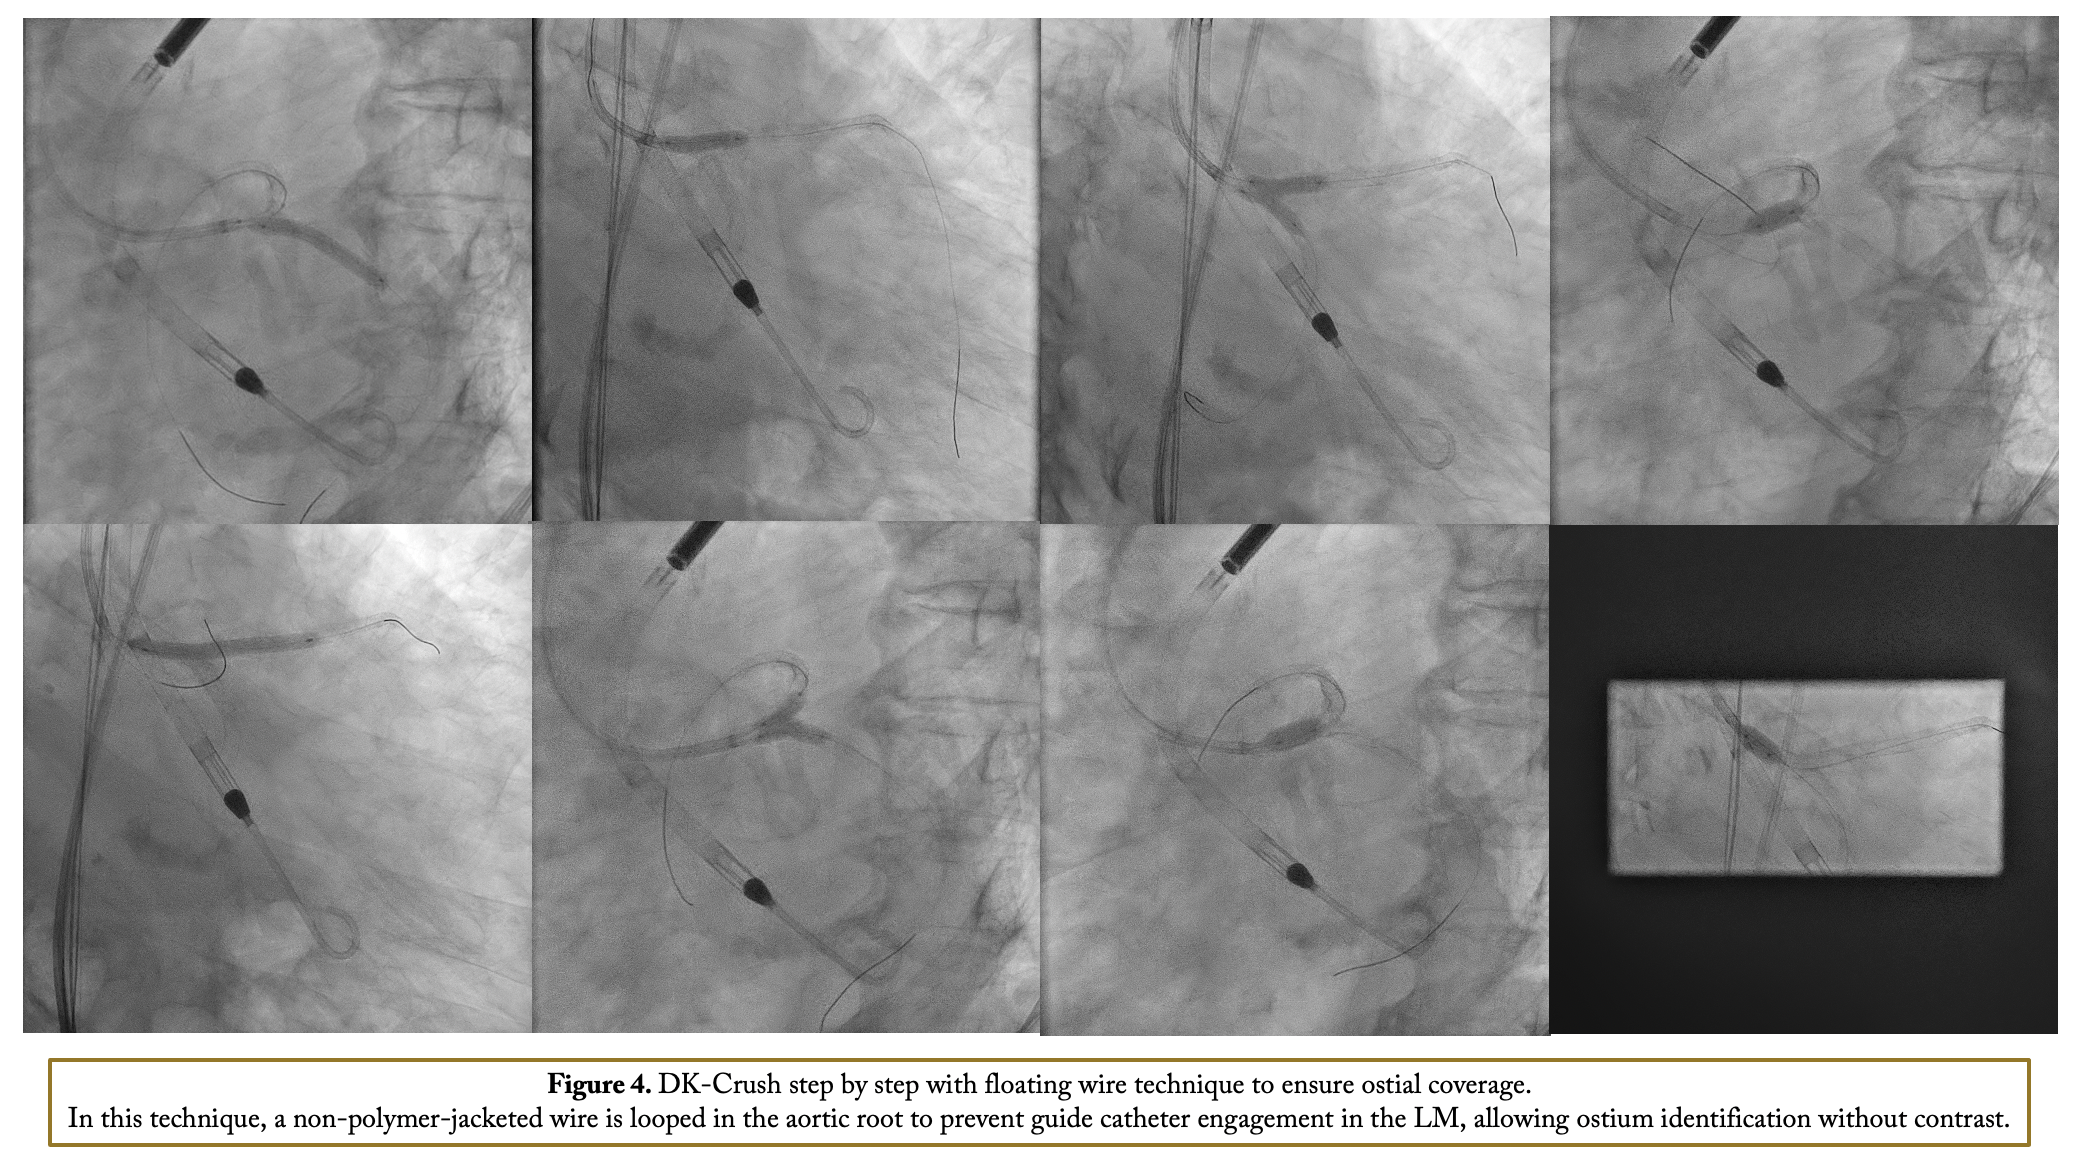

After confirming iliofemoral anatomy suitability for Impella via intravascular ultrasound (IVUS), right femoral access was obtained with a 14-Fr introducer and two suture-mediated closure devices. Diagnostic angiogram views were set as static monitor images. A 7-Fr sheath was inserted through the Impella introducer, and an EBU 3.5 7-Fr guide catheter engaged the left main coronary without contrast, aided by pressure damping, calcification identification, ECG changes, and wire probing. Co-registration with IVUS was performed using the Eagle Eye IVUS catheter, the only device compatible with the Syncvision co-registration system. IVUS imaging of the left main-LAD revealed fibrocalcific plaque with up to 360-degree calcification in the LM-LAD and LCx. Stent landing zones and vessel sizes were identified, and IVUS imaging of the LCx confirmed severe ostial disease. Rotational atherectomy was done with a 1.5 mm burr in both LAD and LCx. Intravascular lithotripsy (IVL) with a 4.0 mm balloon was applied in the ostial LCx and LM with 120 pulses. The LM bifurcation was treated with a DK crush technique with a non-polymer-jacketed wire is looped in the aortic root to prevent guide catheter engagement in the LM, allowing ostium identification without contrast Final IVUS and angiogram showed good outcomes with stable hemodynamics via Impella support. Hemostasis was achieved with Proglide sutures after device removal.